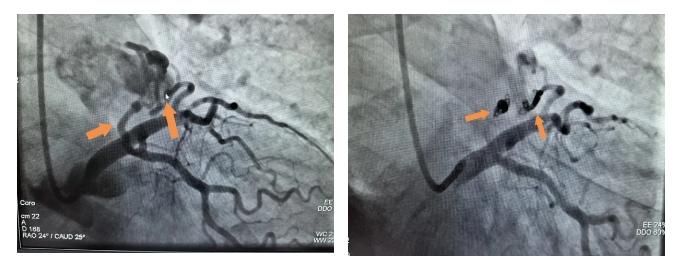

【点击阅读原文】冠心病介入治疗更精准!奉贤区中心医院一次操作实现双模成像2024年7月6日,77岁徐阿姨因为胸痛就诊于奉贤区中心医院心内科,冠脉造影结果并不是大家认为的冠脉狭窄,而是心里藏了两个小偷(冠状动脉瘘)。乔增勇团队选择介入下行冠状动脉瘘弹簧圈封堵术,术后造影提示瘘口被封堵完全。术后徐阿姨冠脉的血不再被偷走,胸痛也消失得无影无踪。